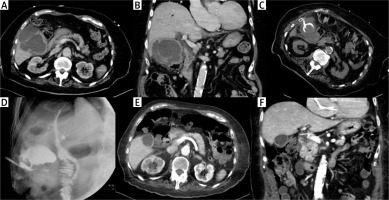

Photo 3

Cholecystostomy in case of acute cholecystitis complicated with surrounded perforation. Preprocedural contrast medium enhanced CT revealed several inflammatory fluid collections around the gallbladder in the transversal (A) and coronal plane (B). The drain was inserted using a transabdominal approach (C). Cholecysto-cholangiography through the drain was performed 7 days after the procedure and revealed no biliary peritonitis; the biliary tract was unobstructed (D). Contrast medium enhanced CT in transversal (E) and coronal plane (F) after 3 months confirmed an almost normal gallbladder pattern